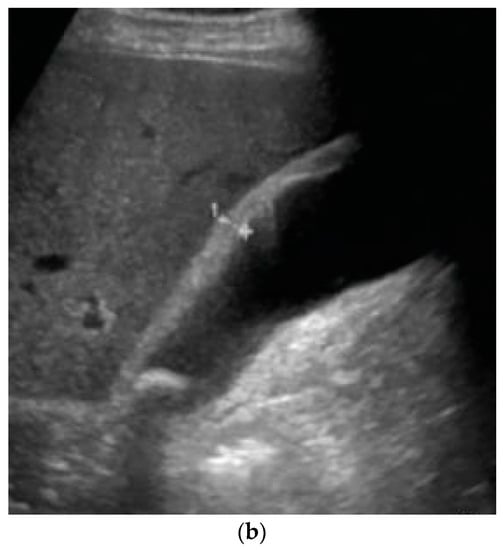

Complications

5. Diagnosis